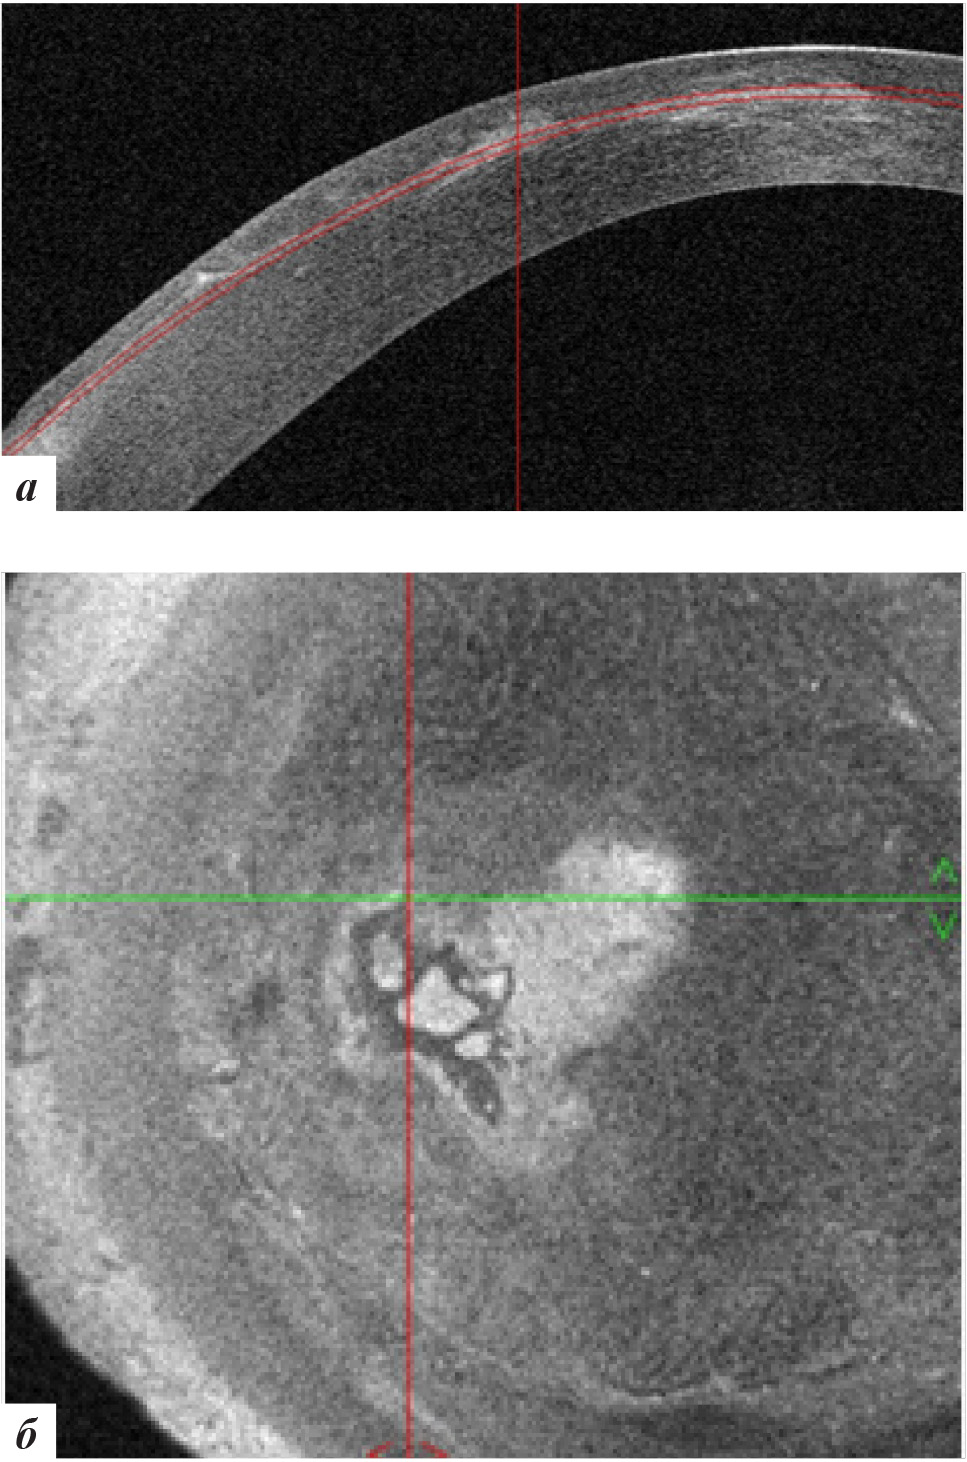

Высота вросшего эпителия по данным ОКТ роговицы уменьшилась (рис. 7). Пациентке было рекомендовано продолжение наблюдения.

Рис. 7. Данные ОКТ роговицы левого глаза через 3 месяца после лечения: а – горизонтальная проекция, б – фронтальная проекция